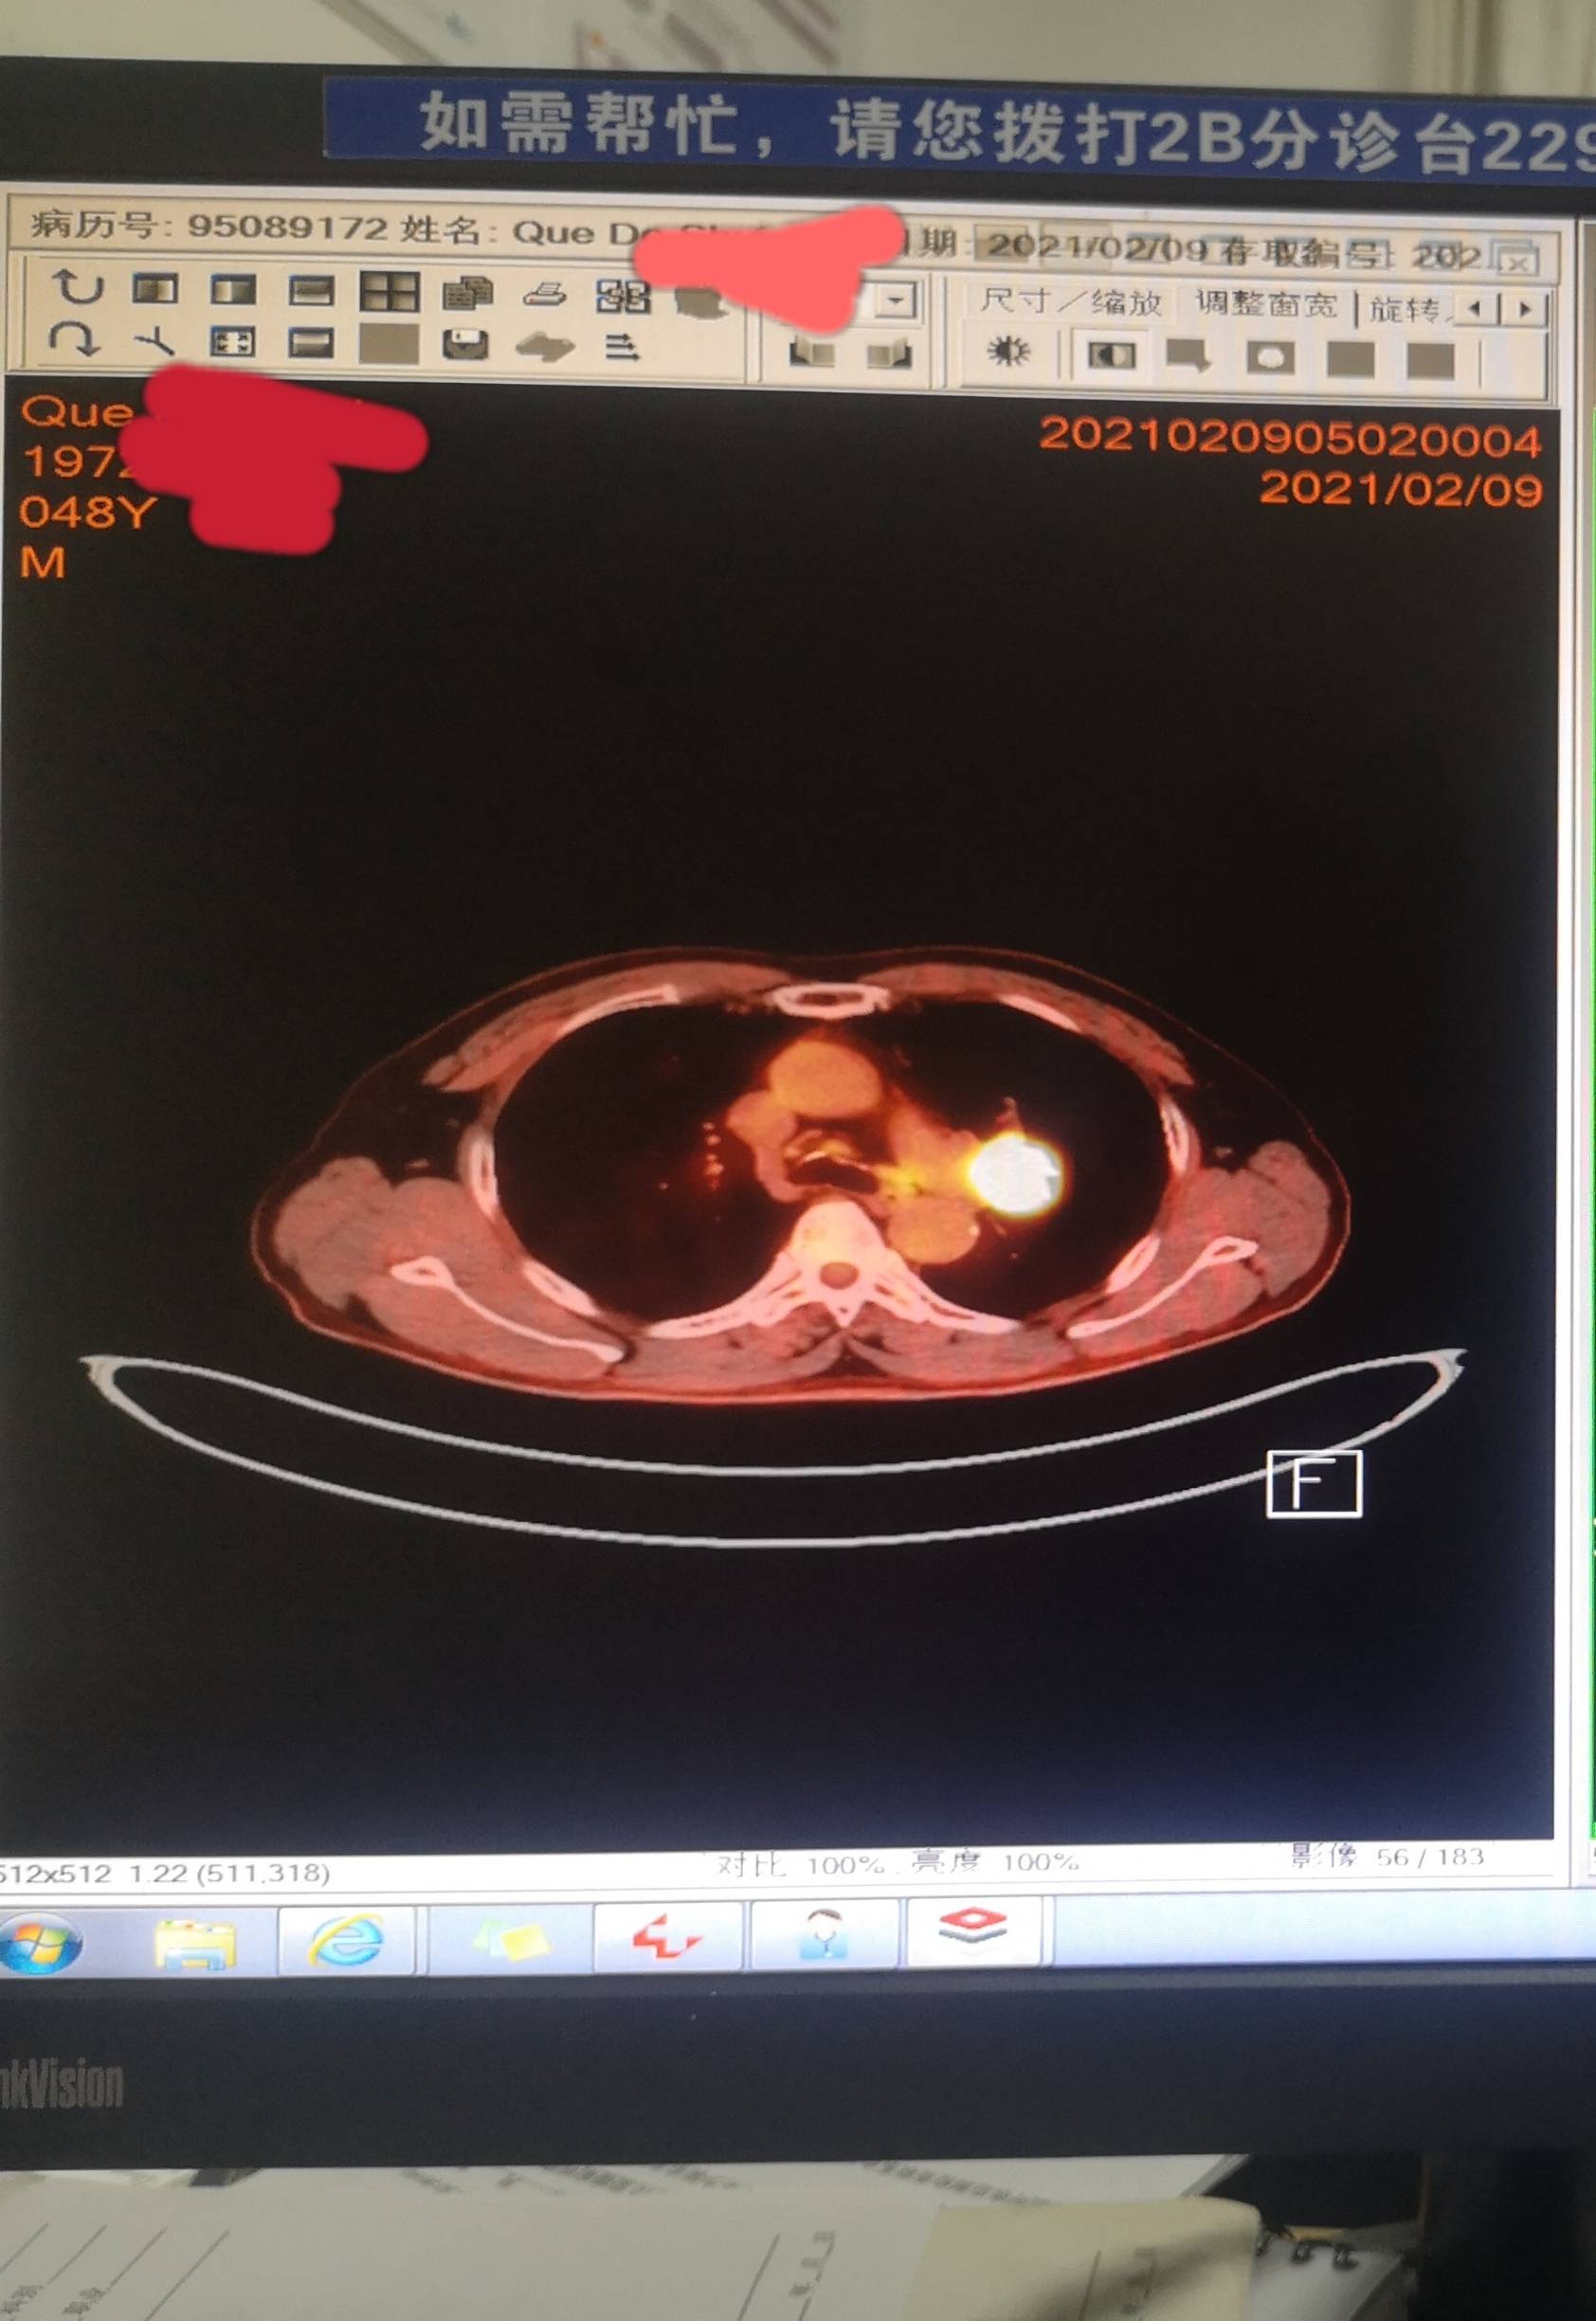

一患者考虑3a或者3b分期的鳞癌,病灶紧贴肺门血管,外科判断暂不能手术,需要新辅助治疗。故前来咨询陈某某医生术前新辅助方案。

患者穿刺小标本PDL1低表达,无敏感用药的基因突变

患者拿不定主意,还是先用白紫加铂做了第一周期术前新辅助化疗,因为比较担心,一周期后,做第二次化疗前就提前复查了一次CT,效果似乎不理想